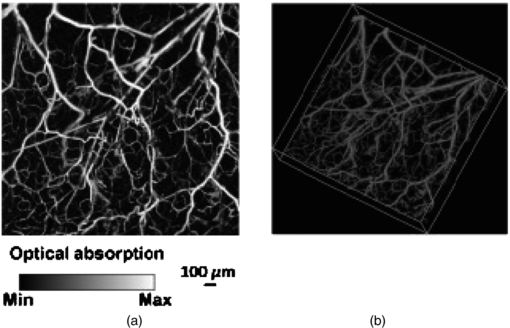

Standard image High-resolution image3.4. Hyperspectral imaging

Hyperspectral imaging (HSI) is a new optical imaging method that can map tissue e.g. oxygen saturation levels, for example to study microvascular perfusion in skin (Lua and Fei 2014). HSI is a spectroscopy technique originally developed for military and geological remote sensing applications giving distinct spectroscopic 'fingerprints' for different molecules. More recently there has been interest in developing aspects of the technology for biomedical applications, e.g. the detection and segmentation of cancer and the measurement of tissue oxygenation relating to haemoglobin in perfused tissues (Sorg et al 2005, Kiyotoki et al 2013). Other applications of HSI include sickle cell disease (Zuzak et al 2003), ophthalmology (Patel et al 2013), diabetes (Nouvong et al 2009), and wound healing (Jafari-Saraf et al 2012).

3.4.1. Background

HSI is based on a spectroscopic technique and involves the generation of a 'hyperspectral' cube stack of spatial and spectral information. This '3D' data cube set comprises, at each pixel of the image, a full spectrum. The spectra generated would depend on both target illumination and detector characteristics. In practice, the field of view is externally illuminated with a broad spectrum light source, with uniform 'white light' illumination across the visible wavelengths (400–700 nm). The illumination can also extend to near infrared depending on what tissue is being studied.

A key medical application of HSI is the spatial non-invasive measurement of tissue oxygen saturation (SO2). Although there are spot measurement devices commercially available that can measure SO2 in skin, these are contact based and localized. The contact pressure can add to the uncertainty in the values measured. Furthermore, there are clinical applications where sterile non-contact methods are required such as in burns assessment and wound healing. HSI can calculate SO2 from established methods by comparing absorption spectra in the green part of the spectrum where high oxygen saturation in tissue haemoglobin has a pulsatile spectrum whereas reduced haemoglobin is monophasic and damped (figure 27).

Figure 27. Tissue oxygen saturation levels can be obtained using wavelengths in the green wavelength range. Haemoglobin that has high levels of tissue oxygen saturation (HbO2) has a pulsatile spectral response whereas reduced haemoglobin (Hbr) has damped spectra. Interpolation techniques can be applied from absorption spectra at key wavelengths to give a measure of tissue oxygen saturation (SO2).